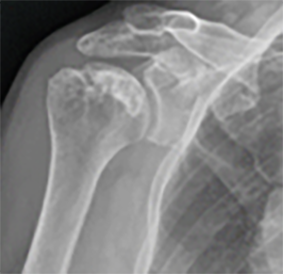

어깨 역행성 인공관절수술

둥근 상완골 끝에는 오목한 소켓 모양의 인공관절 부품을, 오목한 부위에는 볼록한 공 모양의 인공관절 부품을 사용하여 삼각근을 이용해 팔을 들어올릴 수 있게끔 치료를 시행하게 됩니다.

역행성인공관절(수술전)